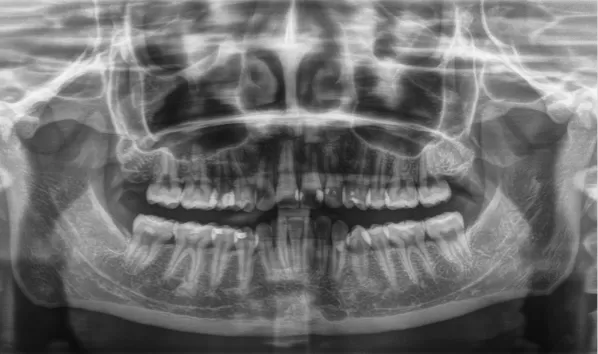

X-rays before treatment

[Panoramic Radiography/Lateral Cephalogram]